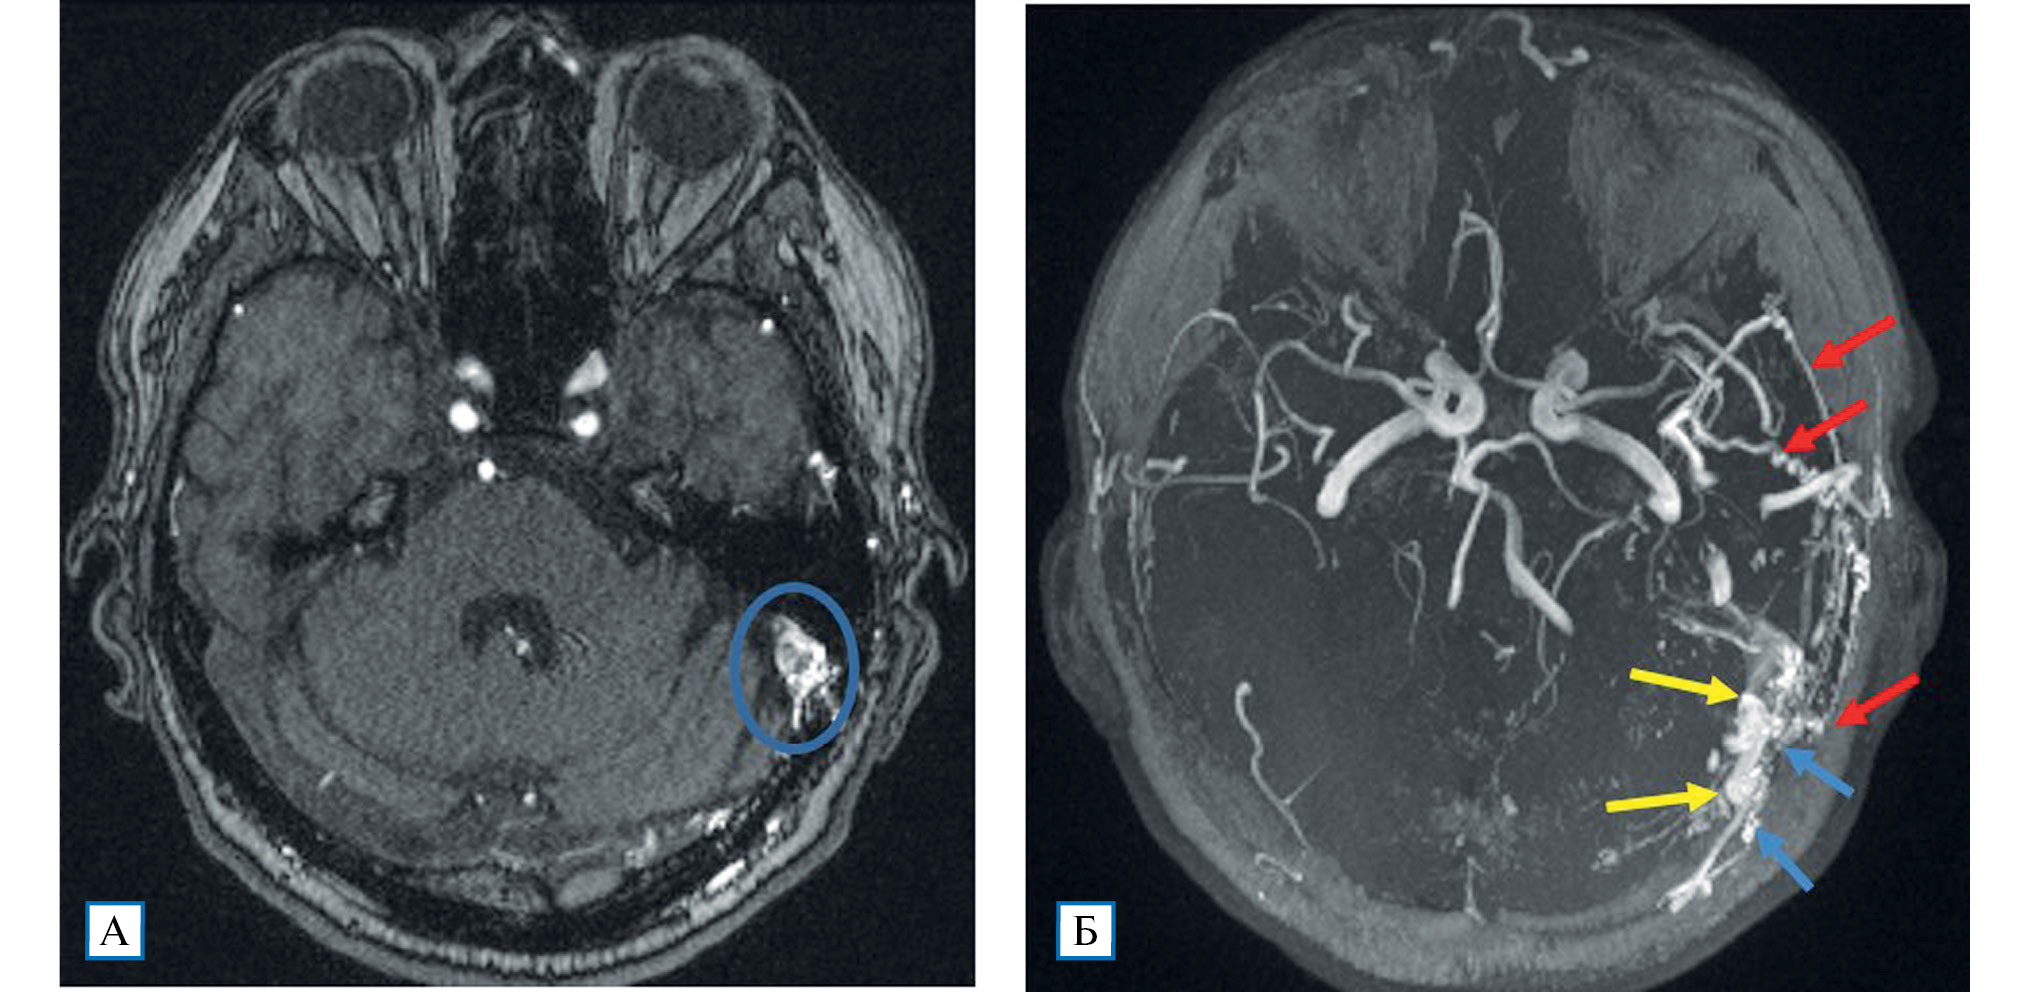

Проведенное дуплексное сканирование сосудов головы обнаружило признаки артериовенозной мальформации в бассейне левой наружной сонной артерии с артериализацией и усилением кровотока по внутренней яремной вене. Усиление скорости кровотока по задней околоушной артерии позволило предположить ее в качестве «питающего» сосуда (рис. 1). Контрастная МР-ангиография подтвердила наличие артериовенозного соустья с вовлечением поперечного и частично сигмовидного синусов слева (рис. 2).

Рис. 2. МР-ангиография (3D TOF-ангиография)

Примечание. А — сброс крови из ветвей наружной сонной артерии в левый поперечный синус; Б — аксиальная MIP-реконструкция: визуализируются нормальные артерии Виллизиева круга; слева расширенные и извитые ветви наружной сонной артерии (алые стрелки), из которых происходит сброс крови в поперечный и сигмовидный синусы (желтые стрелки), извитость и расширение дуральных вен вследствие полнокровия (голубые стрелки).